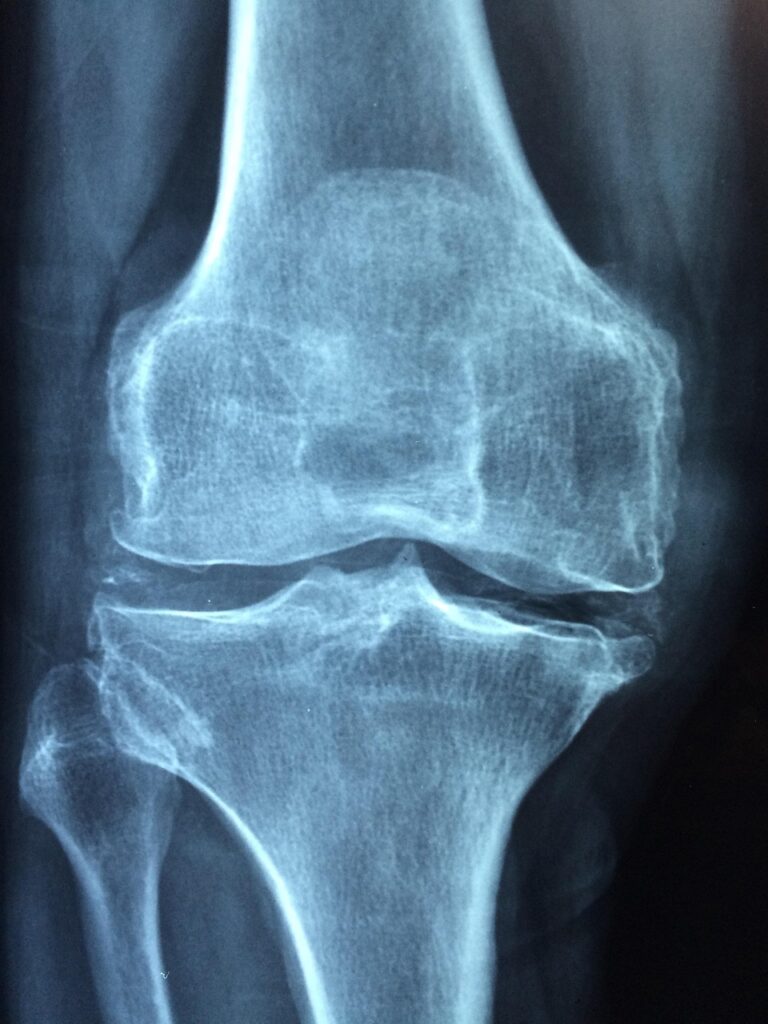

梅雨の季節になると、膝痛が悪化する方が多いと聞きますね。あなたもそんな悩みを抱えていませんか?特に湿気が多くなるこの時期、関節に不調を感じる方は少なくありません。では、なぜ梅雨の時期に膝痛が悪化するのか、その原因を探ってみましょう。

梅雨の季節は、湿度が高くなるため、身体にさまざまな影響を及ぼします。湿気は関節に負担をかける要因の一つです。具体的には、以下のようなことが考えられます。

これらの要因が重なることで、膝痛が悪化することがあるのです。あなたも、梅雨の時期に特に膝が痛むと感じることがあるかもしれませんね。